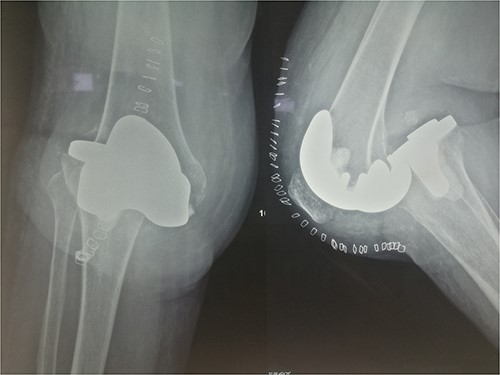

The external fixator was removed after 6 weeks (Fig. 6), and physical therapy was initiated. The patient’s postoperative course was uncomplicated. One week upon removal, 0°–80° of flexion was achieved through everyday kinesiotherapy. On her last visit, 1 year postoperatively, the patient was ambulatory, with knee ROM of 0°–100° (Fig. 7). No further abnormal neuromuscular signs were observed.